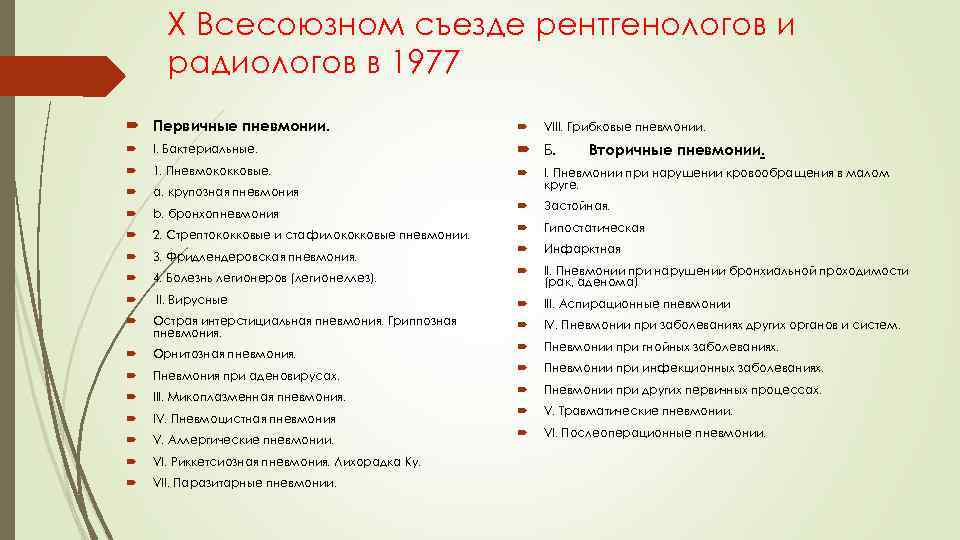

X Всесоюзном съезде рентгенологов и радиологов в 1977 Первичные пневмонии. VIII. Грибковые пневмонии. Вторичные пневмонии. I. Бактериальные. Б. 1. Пневмококковые. a. крупозная пневмония I. Пневмонии при нарушении кровообращения в малом круге. b. бронхопневмония Застойная. 2. Стрептококковые и стафилококковые пневмонии. Гипостатическая 3. Фридлендеровская пневмония. Инфарктная 4. Болезнь легионеров (легионеллез). II. Пневмонии при нарушении бронхиальной проходимости (рак, аденома) II. Вирусные III. Аспирационные пневмонии Острая интерстициальная пневмония. Гриппозная пневмония. IV. Пневмонии при заболеваниях других органов и систем. Орнитозная пневмония. Пневмонии при гнойных заболеваниях. Пневмония при аденовирусах. Пневмонии при инфекционных заболеваниях. III. Микоплазменная пневмония. Пневмонии при других первичных процессах. IV. Пневмоцистная пневмония V. Травматические пневмонии. V. Аллергические пневмонии. VI. Послеоперационные пневмонии. VI. Риккетсиозная пневмония. Лихорадка Ку. VII. Паразитарные пневмонии.

X Всесоюзном съезде рентгенологов и радиологов в 1977 Первичные пневмонии. VIII. Грибковые пневмонии. Вторичные пневмонии. I. Бактериальные. Б. 1. Пневмококковые. a. крупозная пневмония I. Пневмонии при нарушении кровообращения в малом круге. b. бронхопневмония Застойная. 2. Стрептококковые и стафилококковые пневмонии. Гипостатическая 3. Фридлендеровская пневмония. Инфарктная 4. Болезнь легионеров (легионеллез). II. Пневмонии при нарушении бронхиальной проходимости (рак, аденома) II. Вирусные III. Аспирационные пневмонии Острая интерстициальная пневмония. Гриппозная пневмония. IV. Пневмонии при заболеваниях других органов и систем. Орнитозная пневмония. Пневмонии при гнойных заболеваниях. Пневмония при аденовирусах. Пневмонии при инфекционных заболеваниях. III. Микоплазменная пневмония. Пневмонии при других первичных процессах. IV. Пневмоцистная пневмония V. Травматические пневмонии. V. Аллергические пневмонии. VI. Послеоперационные пневмонии. VI. Риккетсиозная пневмония. Лихорадка Ку. VII. Паразитарные пневмонии.